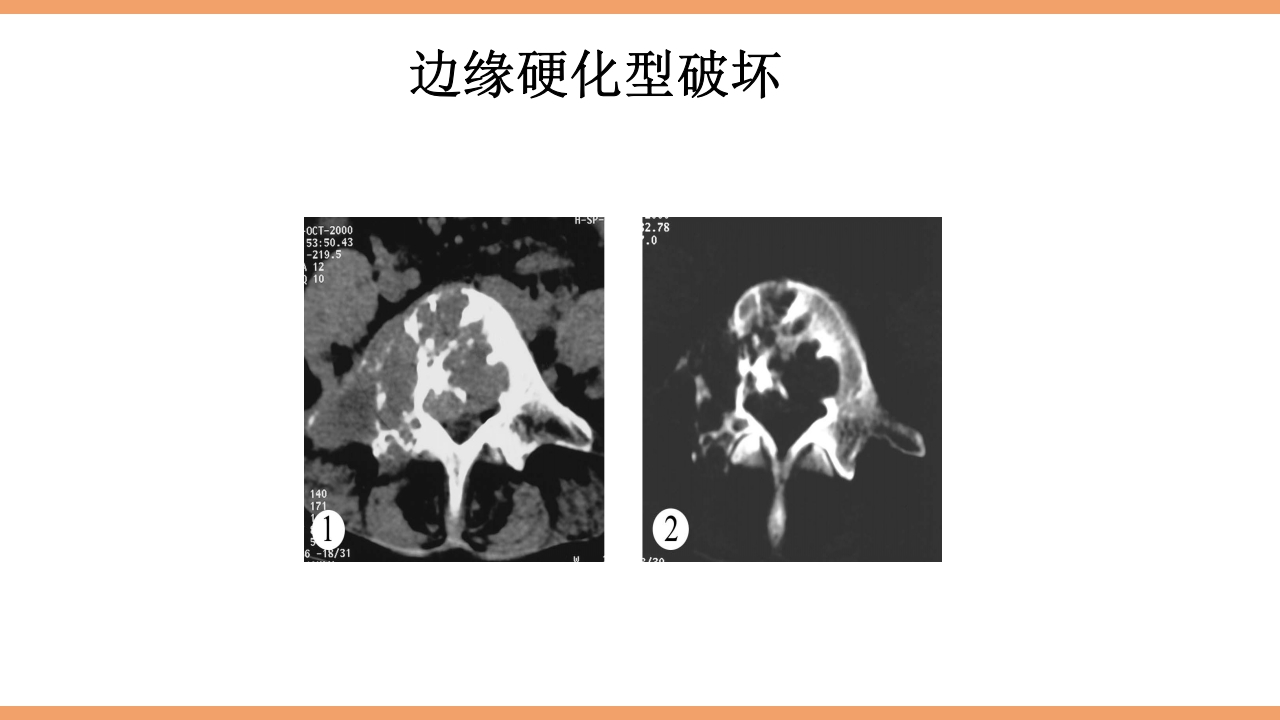

CONTENTS 目 录 1 结核简介 2 脊柱结核概论 3 病灶形成和发展 4 解剖位置 5 病理病因 6 分型 7 临床表现及症状体征 8 影像学及实验室检查 9 治疗 10 护理 11 治愈标准 12 出院指导 西医谓之为: 骨、关节结核:结核病菌侵入骨或关节内并在其中繁殖,出现 一系列的病理改变。 中医谓之为: 骨痨:由于结核杆菌侵入骨或关节而引起的化脓性病变,其病 发于骨,消耗气血津液,导致形体虚赢,缠绵难愈故其名为骨痨。 成脓破溃后,脓液中伴败絮状痰样物,可流窜他处形成寒性脓肿, 又名流痰。骨痨发于脊柱称之为脊柱痨、龟背痰。 胸椎结核为龟背痰,腰椎结核为肾俞虚 痰,骶尾椎结核为尾闾发。 1.脊柱结核是一种继发性病 变,约90%继发于肺结核.少 数继发于消化道结核、胸膜 结核或...